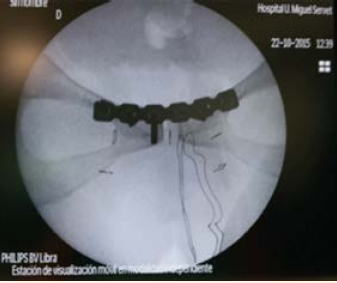

En la reevaluación de los traumatólogos a las 72 horas, éstos decidieron operarla para corregir la afectación de la articulación sacroiliaca, el tamaño de la diástasis, la persistencia de incapacidad funcional y la necesidad de reposo prolongado. A los 6 días posparto se realizó una osteosíntesis con placa y tornillos, a través de una incisión de Pfannenstiel. Figuras 3 y 4

Figura 3 Radiografía de pelvis antero-posterior intraoperatoria que muestra la colocación de la osteosíntesis con placa y tornillos para la reducción de la diástasis.